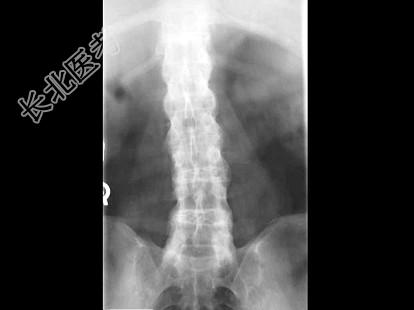

- 单项选择题男,21岁, 腰部不适,晨起加重半年余, X线检查如图,最可能的诊断是 ( )

A、类风湿关节炎

B、脊椎退行性变

C、强直性脊柱炎

D、化脓性脊柱炎

E、阻滞椎